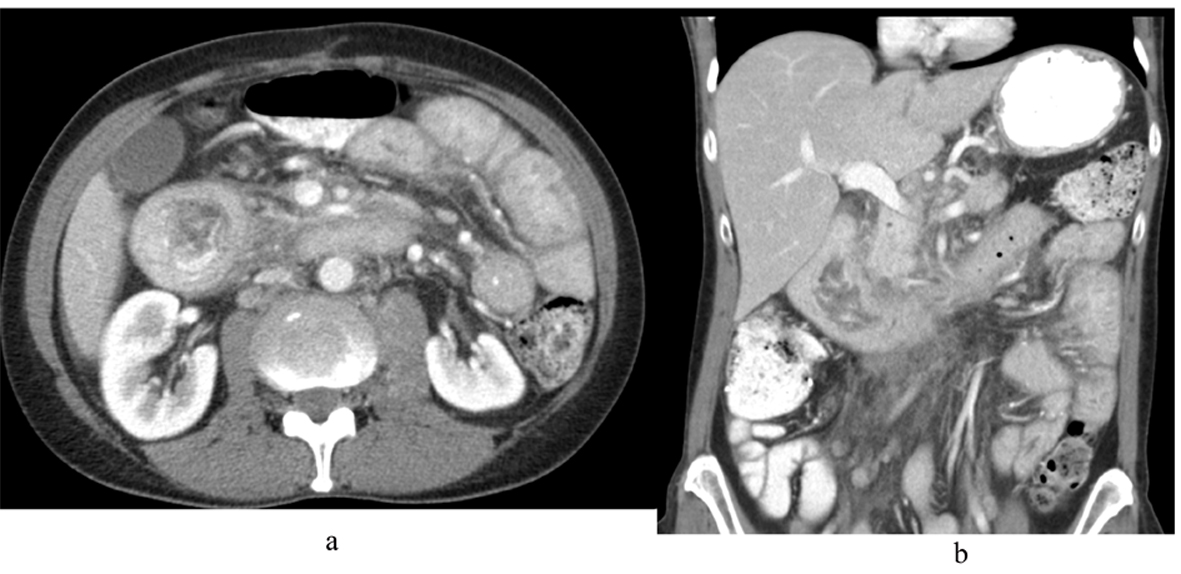

During the current presentation, CT scan of abdomen and pelvis with intravenous (IV) contrast revealed marked distention with irregular wall thickening of the duodenum just proximal to the genu causing a partial gastric outlet obstruction (Fig. 1). It also showed enlarged lymph nodes within the small bowel mesentery as well as the retroperitoneum, concerning for recurrent malignant disease.

![]() Click for large image | Figure 1. CT scan of abdomen and pelvis with IV contrast (A) axial view and (B) coronal view showing marked distention with irregular wall thickening of the duodenum just proximal to the genu causing a partial gastric outlet obstruction. |